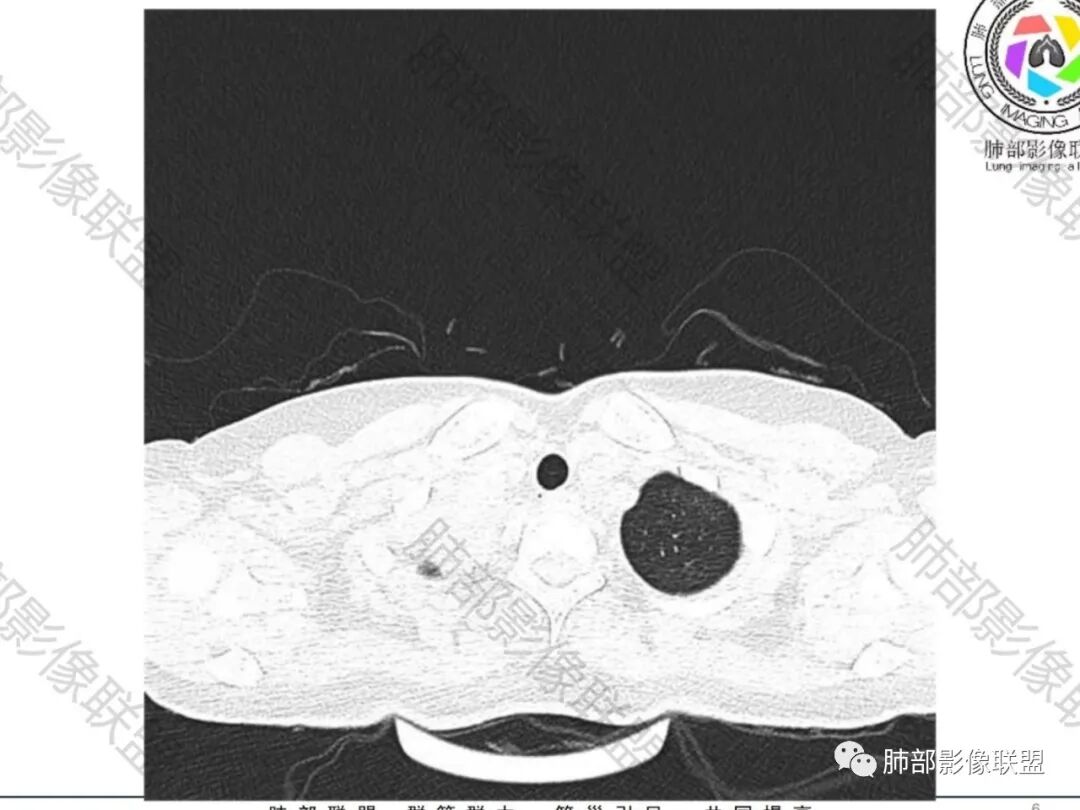

尘缘:青年女性,痰中带血,胸痛2月,无发热盗汗,实验室检查,有贫血,总蛋白降低,血沉情况未知,肿标基本正常。影像表现:双上肺小叶间隔增厚,双侧胸膜广泛不规则增厚,胸膜下多发肿块伴不规则钙化,右侧肋骨破坏。纵隔淋巴结肿大不明显,双肺门淋巴结肿大,部分融合,分析思路:一、感染性病变,1、结核,青年女性,胸膜增厚,多发肿块伴钙化,有咳嗽胸痛,痰中带血,要考虑,但无结核中毒症状,病史仅两月却钙化太明显,肺内没有明显树芽征,存疑,2、其他感染,无炎性指标支持,白细胞不高,可能性小。二、非感染性病变,1、尘肺,胸膜增厚,钙化,胸膜下钙化性肿块,要考虑,但肺内无粉尘结节,无职业史,可能小。2、转移性钙化,无肾脏病史,无血清钙磷代谢异常指标支持,肺内间质无钙沉积改变,基本排除。三、肿瘤性病变,1、肺癌伴转移,双上肺有小叶间隔增厚,双肺门有淋巴结肿大,要考虑,但青年女性,病史两月,钙化太多太广泛,肿标基本正常,可能性小。2、骨肉瘤转移。15-30岁青年人,是骨肉瘤高发年龄,肺内多发成骨样钙化转移灶,双上肺小叶间隔增厚符合癌淋样表现,右侧肋骨破坏,要高度怀疑,需要详细询问病史及手术史。3、软骨来源肿瘤伴肺内转移,右侧肋骨虽有破坏,但无明显软骨样破坏及钙化。可能小。4、其他肿瘤伴转移,青年女性,其他恶性肿瘤能广泛发生钙化性转移的可能性小。综上所述:骨肉瘤伴右侧肋骨及胸膜转移,胸膜下转移,肺内癌淋可能最大,结核不完全除外,下一步需要,仔细询问病史,如果有骨肉瘤史,则基本确诊,如果没有,需要进一步问询呼吸系统症状,病程,以前的影像对照,了解肾脏情况,查血清钙磷指标。

骨质破坏,但是密度增高

你对比一下髓腔

它这个髓腔密度不对,皮质也欠连续,还是以骨头为主

南边:那就是说这个肋骨是自身的病变,有成骨性骨质破坏

肋骨伴随有溶骨性/成骨性骨质破坏,常规还是要警惕恶性